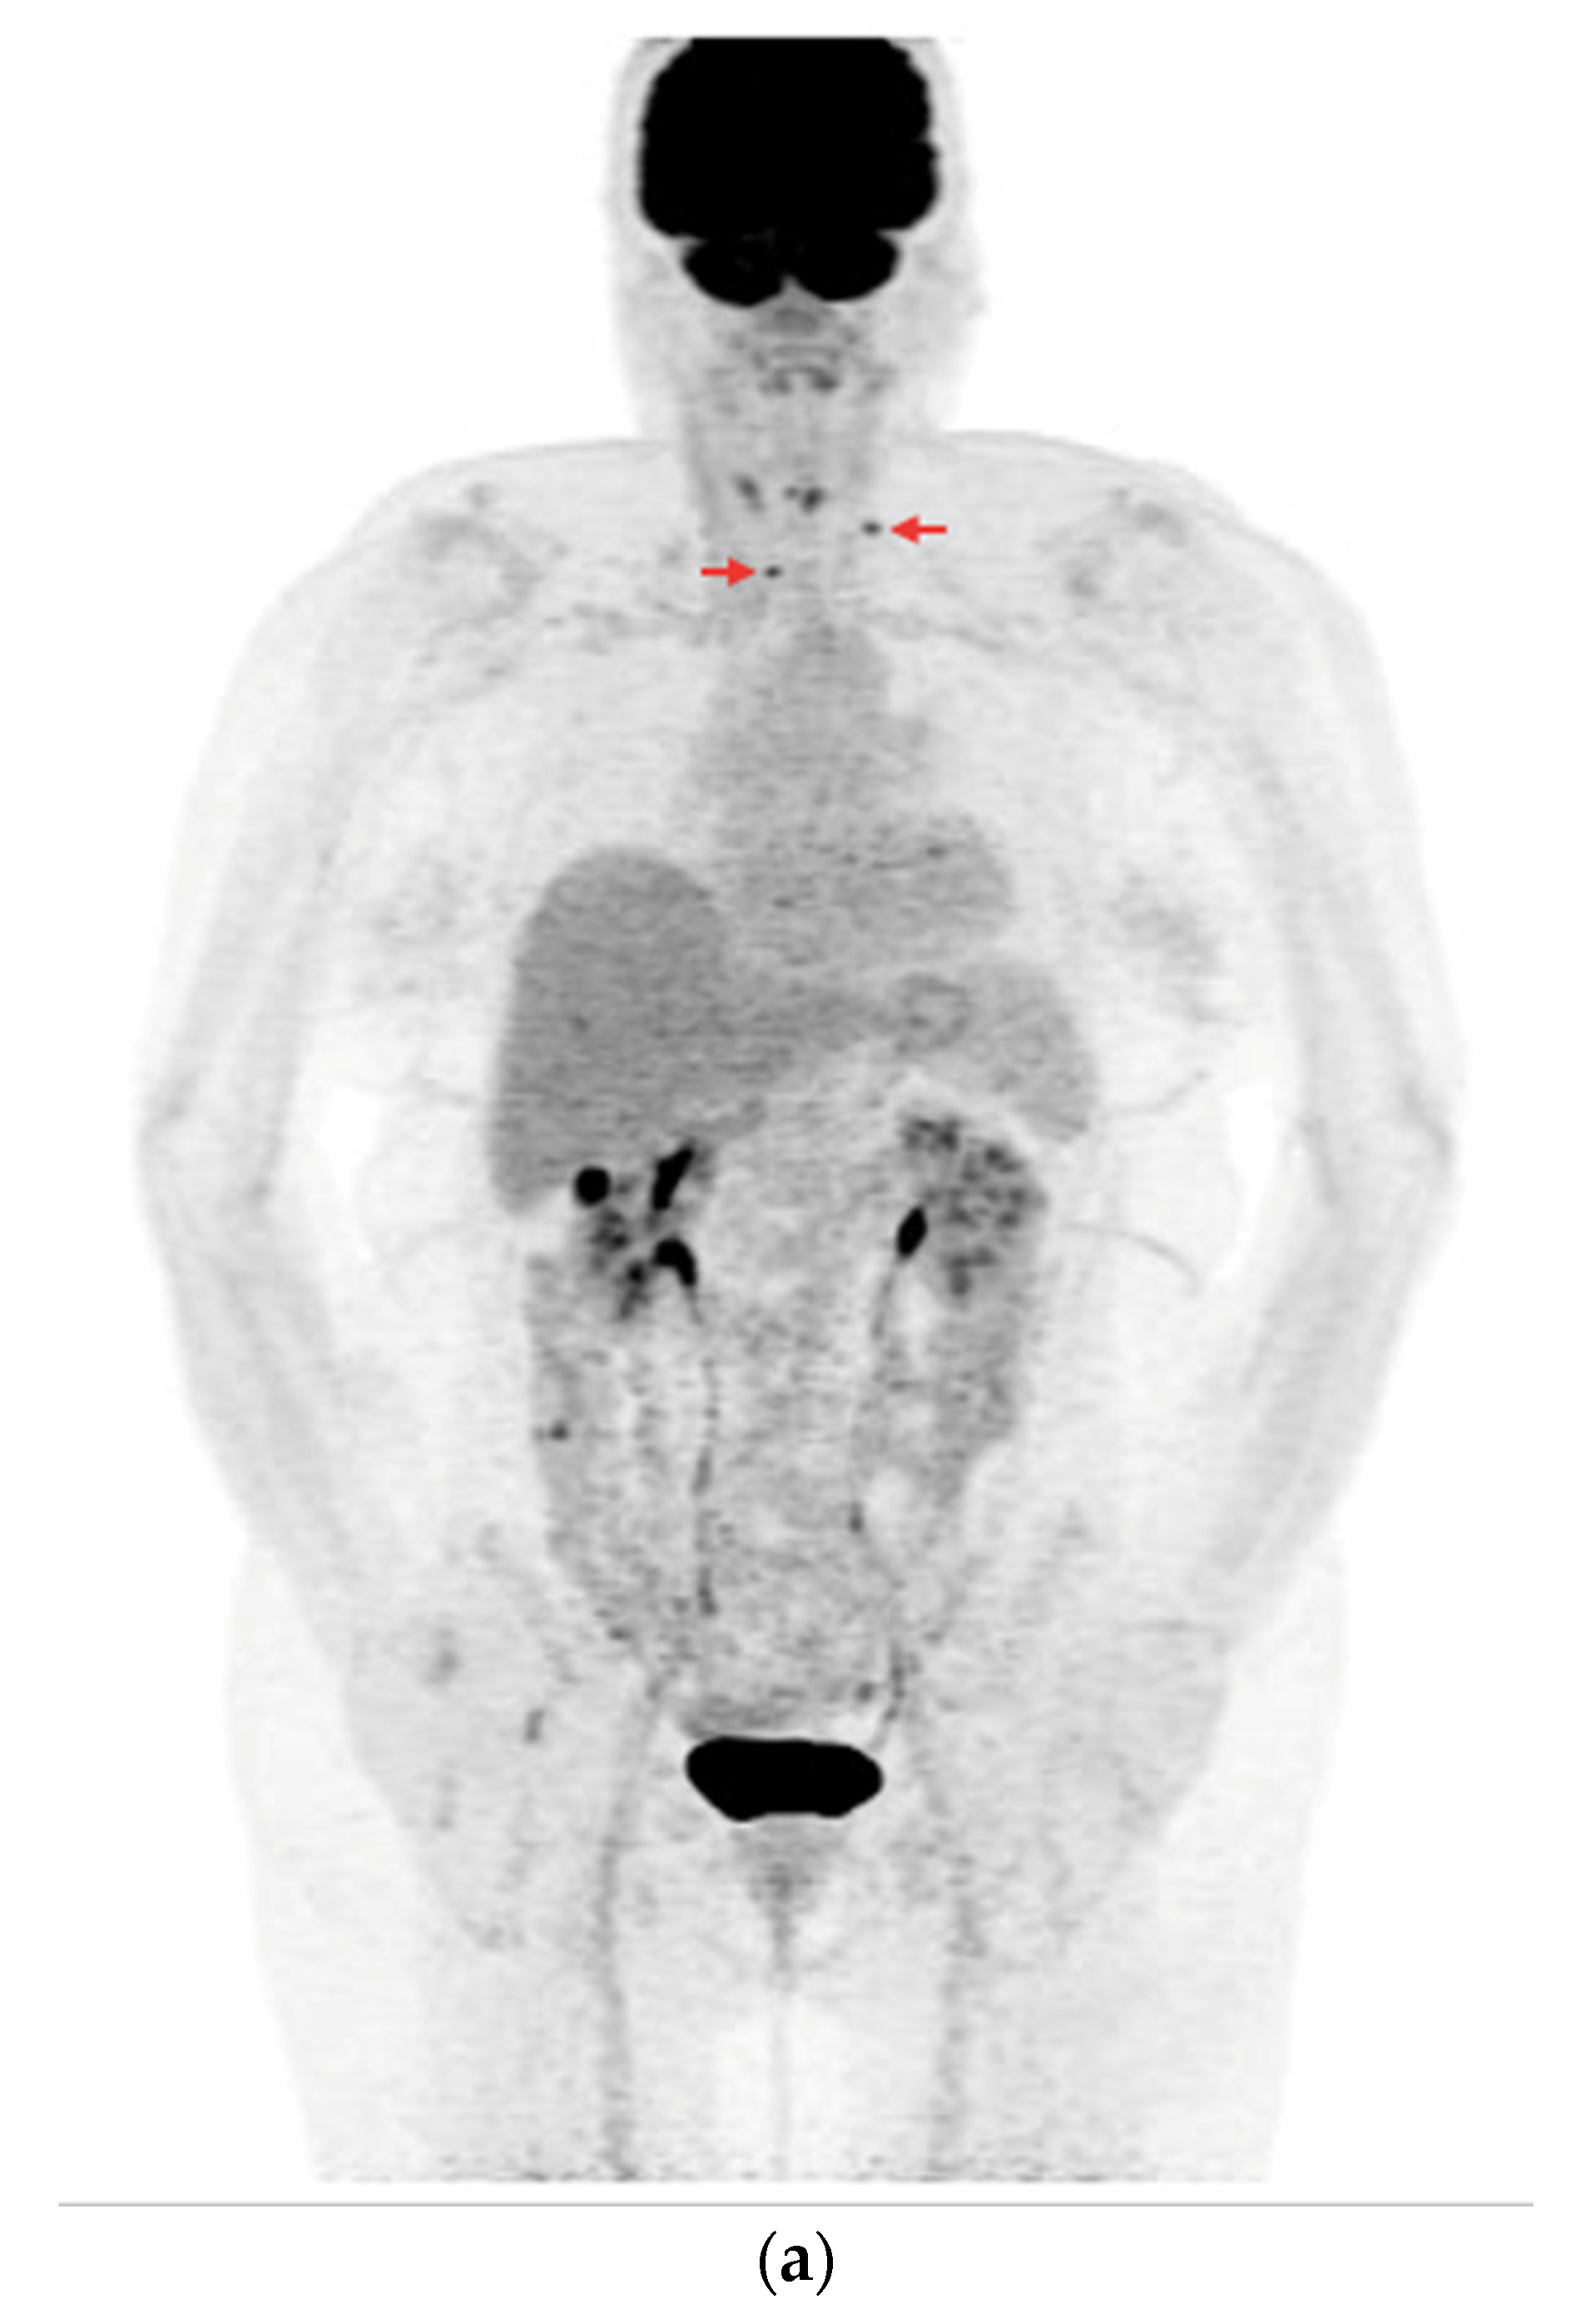

- In the case of non-resectable lesions (due to a lack of the patient’s consent to repeated surgery, lack of technical possibilities of surgery or other reasons), the lesions were verified using FNA only, and after verification, the patients remained in the observation group or were referred to tyrosine kinase inhibitor (TKI) therapy (Figure 4a,b).

Figure 4. PET/CT with [18F]FDG (a) Maximum-intensity projection (MIP). (b) Axial fusion projection. These show an example of accumulation of the [18F]FDG in the left retroesophageal lymph node (red arrow). The lesion was verified as being metastasized DTC using FNA. Due to comorbidities and the patient’s lack of consent, resection of the lesion was abandoned; the patient was left in the observation group, with a stable Tg concentration in follow-up determinations (maximum natTg concentration 3.91 ng/mL, maximum sTg concentration 19.62 ng/mL).